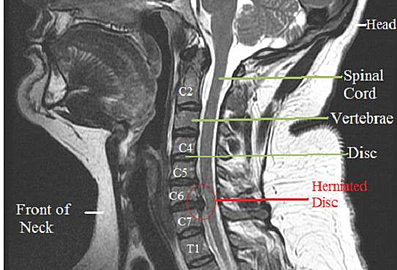

Cervical Herniated Disc - Therapy In Motion

An MRI is the diagnostic test of choice to confirm a cervical herniated disc. Symptoms: Symptoms of a cervical herniated disc depend on the level of Advanced disc herniation can be treated with steroid injections. Some treatment ... Doc Retrieval